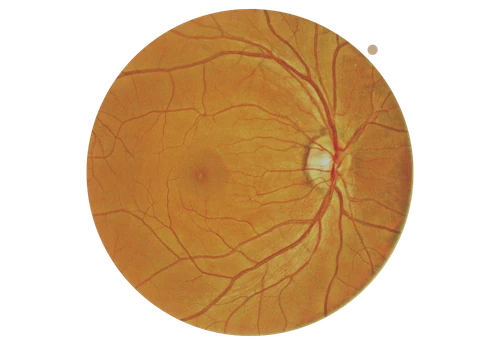

Full colour fundus image

Full-colour fundus imaging delivers a high-resolution view of the posterior segment of the eye for accurate clinical diagnosis. Advanced features such as low flash intensity, fast image capture, automatic blink detection and Small Pupil Mode ensure clear images with minimal discomfort, even during eye movement. Automatic brightness adjustment, adjustable fixation targets and a wide 135° stitched fundus view provide optimal illumination and a comprehensive, low-distortion overview of the retina.